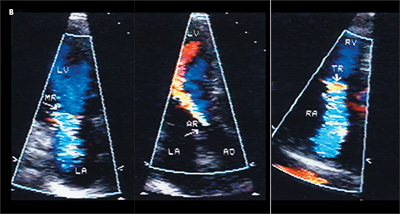

An echocardiographic study showed abnormally thickened and rigid mitral, aortic, and deformed tricuspid leaflets (A). Color flow Doppler images showed abnormal regurgitation at all 3 valves without stenosis (B). Peak right ventricular pressure was 26 mm Hg. Left ventricular function was normal (estimated ejection fraction of 60% to 65%). Because no previous echocardiogram—obtained before the patient started taking the drugs—was available, images of normal cardiac valves are shown for comparison (C).